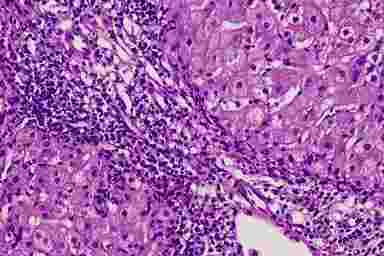

Хронический вирусный гепатит B

Рис. 4.5. Хронический вирусный гепатит B (биоптат печени, окраска г/э, х200). Порто-центральный мостовидный некроз. В зоне некроза - лимфо-гистиоцетарный инфильтрат

Очаги некроза отличаются по локализации и размерам. В дольках наблюдаются мелкие очаги некроза, содержащие клетки инфильтрата (пятнистые некрозы). Более крупные участки некроза – мостовидные, захватывают территорию двух соседних долек. Они делятся на порто-центральные (от портального тракта до центральной вены), см. рис. 4.5, и порто-портальные (от одного портального тракта до другого). Для хронического гепатита В характерны ступенчатые некрозы (рис. 4.6), которые локализуются в перипортальной зоне, на периферии долек и возникают в результате цитопатического действия клеток воспалительного инфильтрата, проникающих сюда из портальных трактов (другое, более позднее название этих изменений – “пограничный гепатит”).